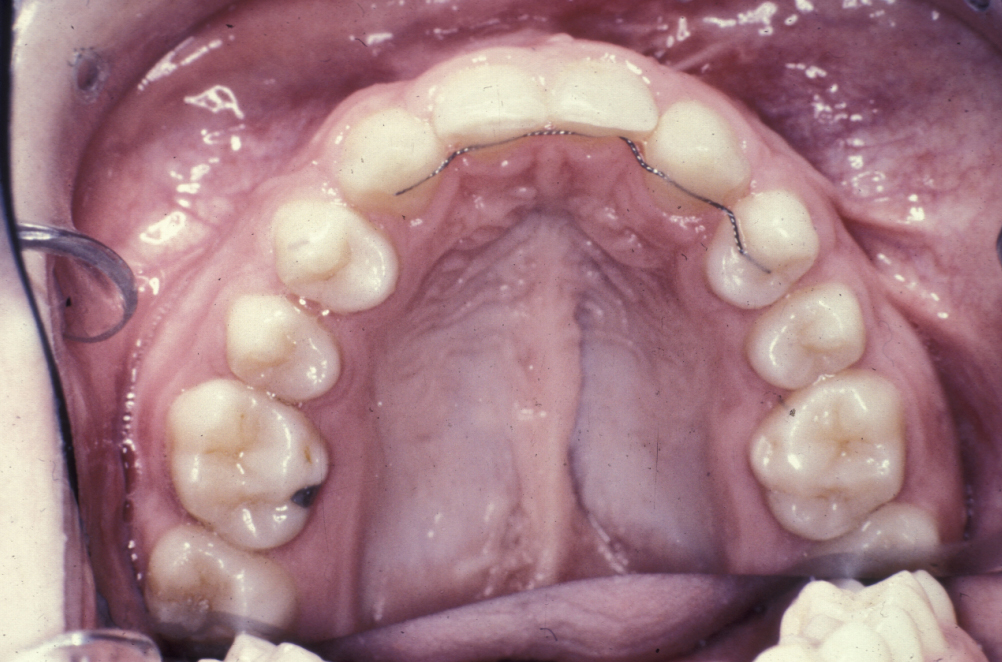

Skull and chin bone are popular in some centres. The bone used should be cancellous bone as this has the greatest propensity to become alveolar bone and allow migration of the canine through it. There is no good evidence to support the use of synthetic materials for this procedure. The periosteum of the lesser segment (larger) buccal flap is then incised and advanced to close the labial defect. It is important to remember that bone will not take against exposed cementum. Therefore, any obviously exposed root (for example from a supernumerary tooth or a residual lateral incisor), should result in removal of that tooth, rather than compromising the bone graft (Figure 7).

Figure 7: The long-term result; surgery without orthodontics is a waste of time. Here the teeth have been aligned after palate and alveolus repair.